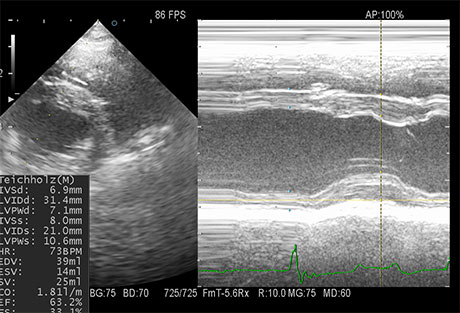

心臓超音波検査

心臓内部の構造や血液の流れを評価します。循環器病を診断するのに最も重要な検査のうちの一つです。